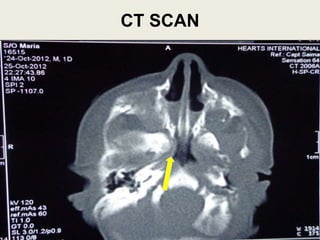

CT SCAN

 CT scan paranasal

sinus with contrast for

delineation of

Choanal atresia

confirmed the

diagnosis of bilateral

choanal atresia of

bony type